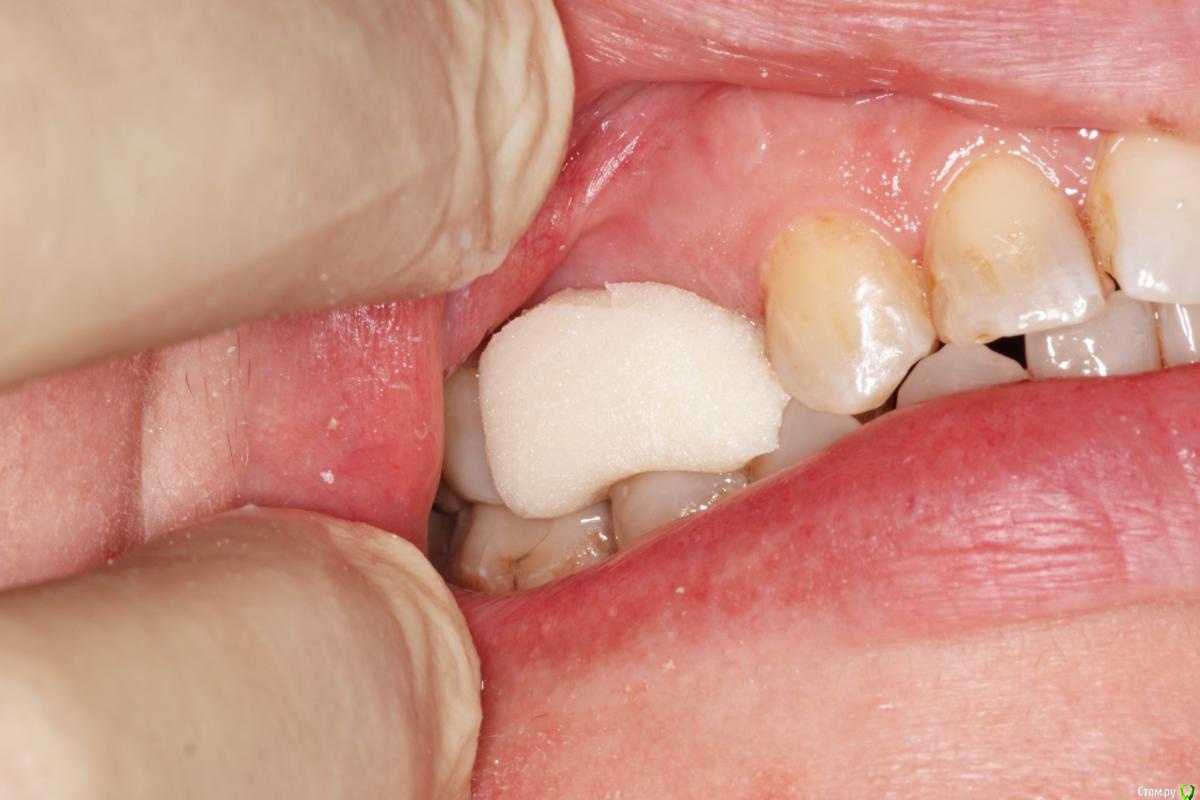

skeettrap Опубликовано 5 июля, 2016 Поделиться Опубликовано 5 июля, 2016 Стандартная ситуация : коллега попросила сделать родственнице (мужа) за неделю - во время краткосрочного визита из Израиля.Исходная ситуация 14,15 сильно разрушены с временными пломбами и наплывшей десной(фото не сделал).На первом этапе сделаны культевые вкладки прямым методом (десну подрезал бором). Постановка вкладок на следующий день, изготовление временных коронок, снятие слепков. Через 2 дня - фиксация. Ссылка на комментарий

skeettrap Опубликовано 6 июля, 2016 Автор Поделиться Опубликовано 6 июля, 2016 На удлинение времени не было. Главное было проснять. Временные делаю так: после замешивания немного жду, когда начинает полимеризоваться, делаю типа брусочка, даю накусить, немного с боков приминаем (это при открытом рте). До окончательного отверждения несколько раз вынимаю и вставляю. По мере нагрева помещаю в холодную воду.После отверждения формирую предварительно, внутри немного убираю и делаю перебазировку. Окончательно формирую и фиксирую. Ссылка на комментарий